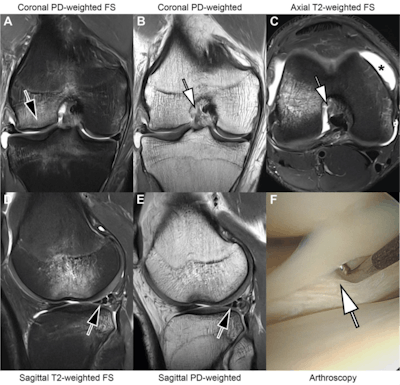

MRI scans in an 18-year-old man with right knee pain following a noncontact twisting injury playing basketball. Combined threefold parallel imaging (PIx3) and twofold simultaneous multislice (SMSx2) accelerated deep learning super-resolution turbo spin-echo sequences (A-E) were acquired at 3 tesla. Coronal proton density (PD) fat-suppressed (FS) (A), coronal PD-weighted (B), axial T2-weighted fat-suppressed (C), sagittal T2-weighted fat-suppressed (D), and sagittal PD-weighted (E) MRI scans demonstrate findings suggestive of a pivot-shift mechanism injury with a transchondral fracture of the central lateral femoral condyle (arrow in A) and transchondral bone contusion of the posterolateral tibial plateau, a femoral attachment full-thickness tear of the anterior cruciate ligament (arrows in B and C), joint effusion (asterisk in C), and a nondisplaced vertical-longitudinal tear along the posterior segment of the lateral meniscus (arrows in D and E). Readers correctly diagnosed the findings. An arthroscopic knee surgery photograph (F) demonstrates the lateral meniscus tear (arrow in F). FS = fat-suppressed. PD = proton density. Images and caption courtesy of the AJR.